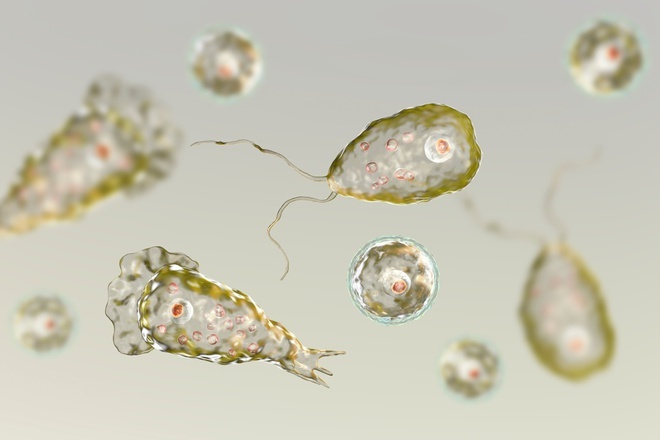

Mỹ bất ngờ công bố ca amip ăn não người siêu hiếm gặp

Cơ quan Y tế Florida (DOH) hôm 3/7 xác nhận ca 'amip ăn não' Naegleria cực kỳ hiếm gặp, một loại amip đơn bào siêu nhỏ có thể xâm nhập và phá hủy não người.